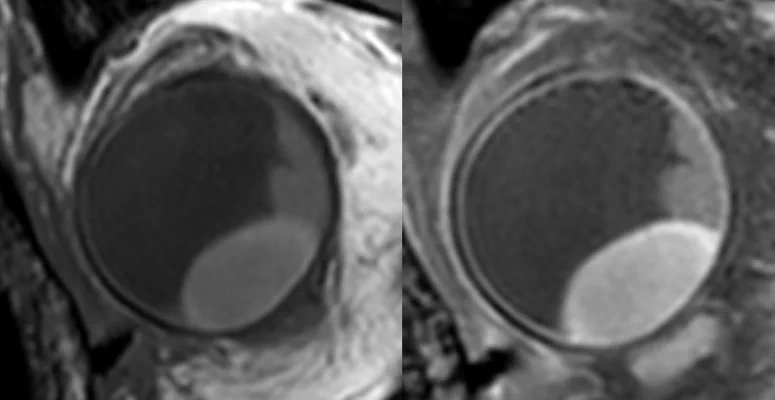

• T1 & T1Gd

T1 & T1Gd

Contrast enhanced scans to differentiate the lesion and retinal detachment.